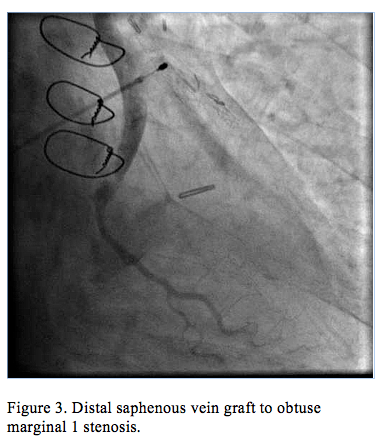

Cardiac catheterization revealed an occluded SVG to OM1 with TIMI flow 0 and possible thrombus (Figure 1, Video 1), a patent LIMA to LAD, an occluded stent within the SVG to Diagonal 1, and a patent SVG to RCA. A 0.014˝ x 135 cm Trailblazer catheter coronary guidewire engaged the SVG to OM1 graft and crossed the lesion. A temporary pacemaker and an intra-aortic balloon pump were placed due to bradycardia and hypotension. A 5 Fr Export catheter was then passed to the thrombus and approximately 15 mL of thrombus were aspirated. Repeat aspiration resulted in a collection of 20 mL of thrombus; however, a significant amount remained (Figure 2, Video 2). A 0.041" x 135 cm TrailBlazer catheter was then advanced to the thrombus and 8 mg of intracoronary abciximab were injected.

Improved flow (TIMI grade 2) was immediately seen, and a discrete lesion was apparent just proximal to the anastomosis of the SVG graft to OM1 artery (Figure 3). A VeriFLEX OTW bare-metal stent was deployed. After postdilatation and injection of 180 mcg intracoronary adenosine, there was TIMI grade 3 flow at the SVG to OM1 (Figure 4, Video 3), ST elevations nearly resolved, and the patient expressed immediate relief of chest pain. Intravenous abciximab was infused (10 mcg/min) for 12 hours postprocedure. Echocardiography the following day revealed severely decreased left ventricular systolic function (ejection fraction <25%) with akinetic inferior, posterior, and anterolateral walls.